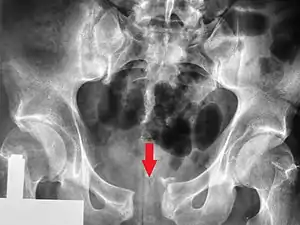

Fratura da bacia

Uma fratura da bacia é uma fratura óssea nos ossos da bacia.[1] Especificamente, o termo denomina qualquer fratura no sacro, nos ossos da anca (ísquio, osso público, ílio) ou no cóccix.[1] O sintoma mais evidente é dor na região pélvica que se agrava com o movimento.[1] Entre as possíveis complicações estão hemorragias internas, lesões na bexiga e trauma vaginal.[2][3]

| Método de diagnóstico | Baseado nos sintomas, confirmado por radiografia ou TAC[1] |